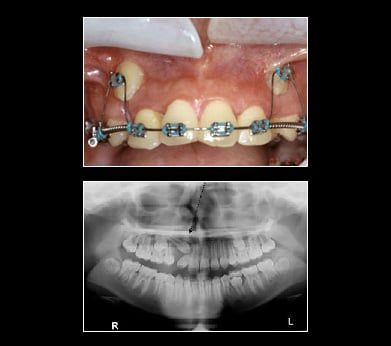

Treatment for Impacted Canines

After assessing your situation, Fresh Smile Dental Practice will devise a plan to make room for your canines. Will a typical oral surgery and the assistance of an orthodontist your canine will find their way into their proper place over time.